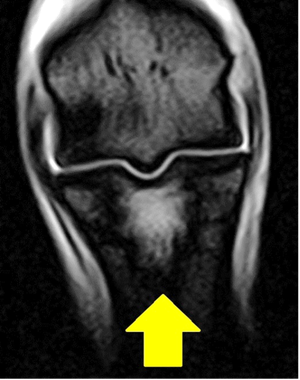

一つ目の症例は6歳の牡馬で、TCでの調教後に跛行を呈しました。球節の関節液増量と屈曲痛および第1指骨背部の圧痛を有したため、球節が原因の跛行と考えられ、初診日とその4日後にレントゲン検査を実施しましたが、明らかな病変は見つけられませんでした。そこで、MRIを実施したところ、第1指骨内に白く光る像が認められました(写真2)。詳しい画像の説明は省略させていただきますが、信号パターンを変えた複数の検査により、本症例は第1指骨内に骨折の前駆病変となる炎症を有すことがわかりました。この結果をもって、数か月単位の馬房内休養を提示しました。このような場合、レントゲン検査によって骨折線を描出できるようになるまで3週間程度かかったり、そもそもレントゲン検査ではいつまでたっても写ってこなかったりします。レントゲン画像で骨折線が認められないからといって、そのまま調教してしまうと骨折の悪化を引き起こす可能性があるので十分注意が必要です。

(球節を前面から撮影しており、矢印で示す第1指骨に白く光る像を認める)